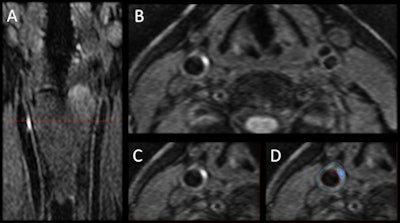

The 3D MRI intraplaque hemorrhage sequence (A) is acquired in the coronal plane. The red dotted line indicates the level at which the reformatted axial plane (B) was obtained. The section of the right carotid artery (C) with a region of high signal is consistent with hemorrhage. Contours are drawn (D) for the outer wall (green) and lumen (red) with the area of hemorrhage (blue). Images courtesy of Dr. Tishan Maraj and RSNA.The researchers cited other contributing factors, such as age, gender, and body mass index, when adjusted for disease duration, smoking status, high blood pressure, and medications including statins.

The participants underwent baseline 3D T1-weighted black-blood imaging for visualization of intraplaque hemorrhage, and 3D time-of-flight imaging to measure carotid artery vessel wall volumes and hemorrhage volumes.

3D MRI revealed the presence of intraplaque hemorrhage in 37 patients (23%), with five individuals (3%) having hemorrhages in both carotid arteries. In addition, vessel wall volume in patients with carotid arteries positive for intraplaque hemorrhage was significantly larger than volume in those with no IPH.